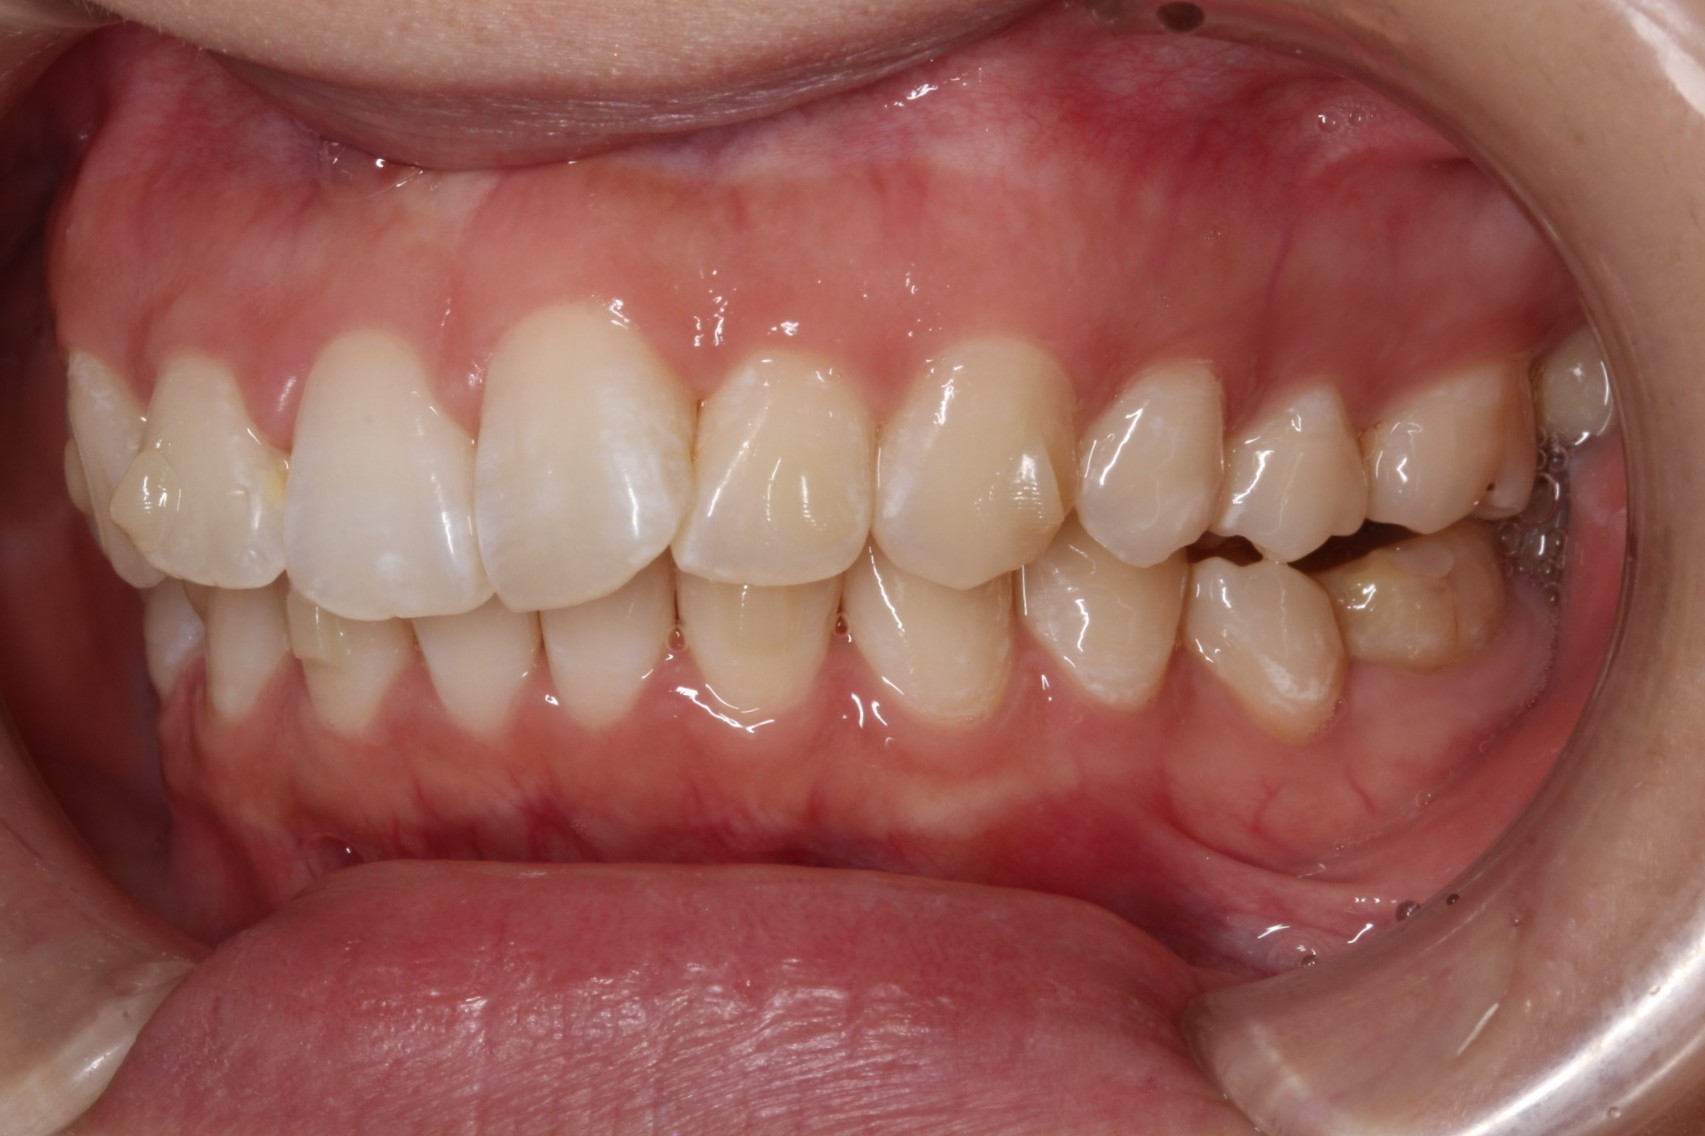

矯正術前:右側

矯正術後:右側